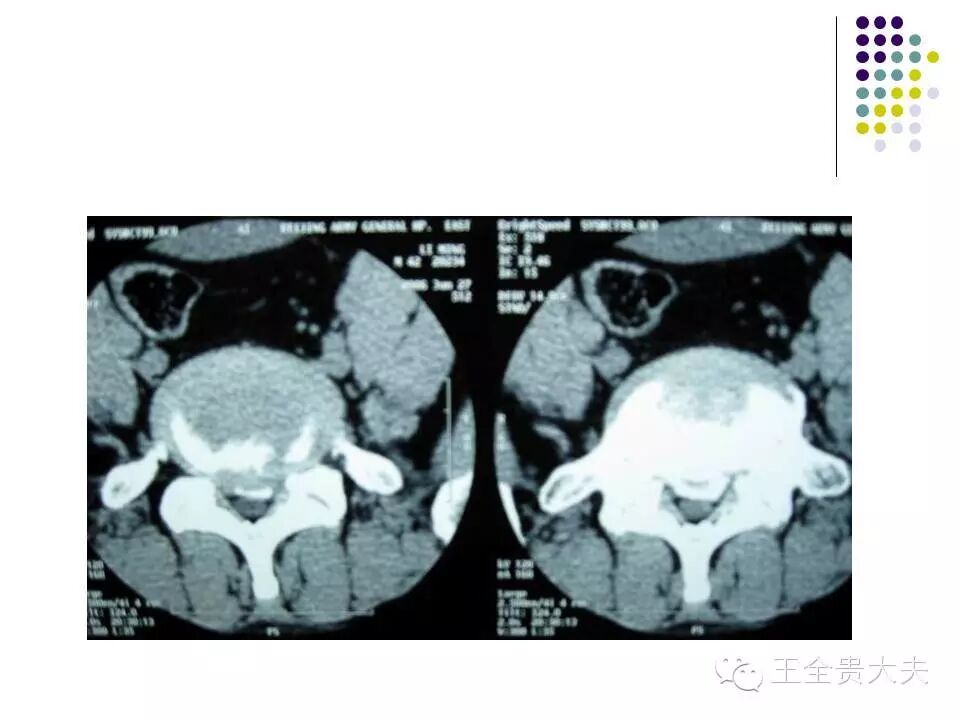

CT的检查原理是X光会分层穿过人体,之后通过电脑计算后二次成像。优点是可以分层看,经计算后可以显示出更多的组织信息。